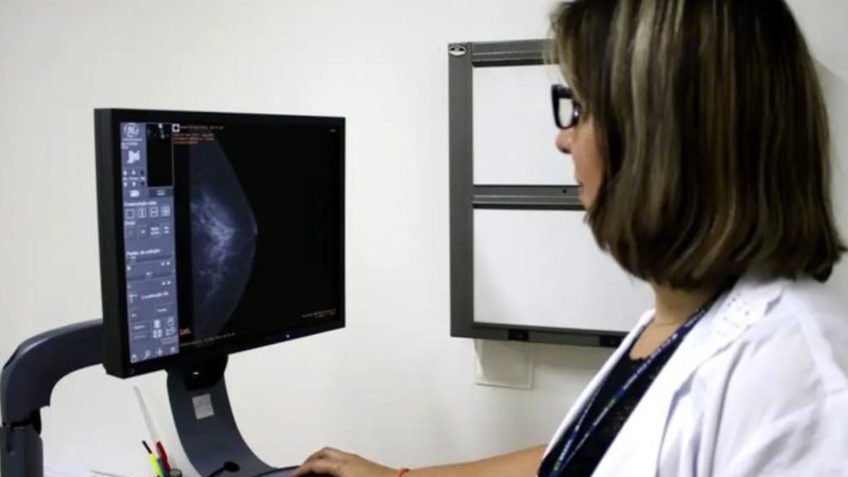

Ministério da Saúde padroniza acesso a exame de mamografia no SUS

Ministério da Saúde padroniza acesso a exame de mamografia no SUS

O Ministério da Saúde publicou nota técnica que define diretrizes para o acesso ao exame de mamografia no SUS (Sistema Único de Saúde).

O rastreamento mamográfico populacional passa a ser recomendado para mulheres de 50 a 74 anos, com realização a cada 2 anos, como estratégia baseada em evidências científicas para reduzir a mortalidade por câncer de mama. Antes, a recomendação oficial era até os 69 anos.